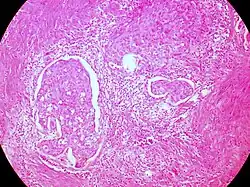

![]() |

Helminth in appendix | Micrograph showing lumen of appendix and cut section of pin worm. | Category: Histopathology of appendix with Enterobius vermicularis | Parasitic helminthiasis infectious disease |